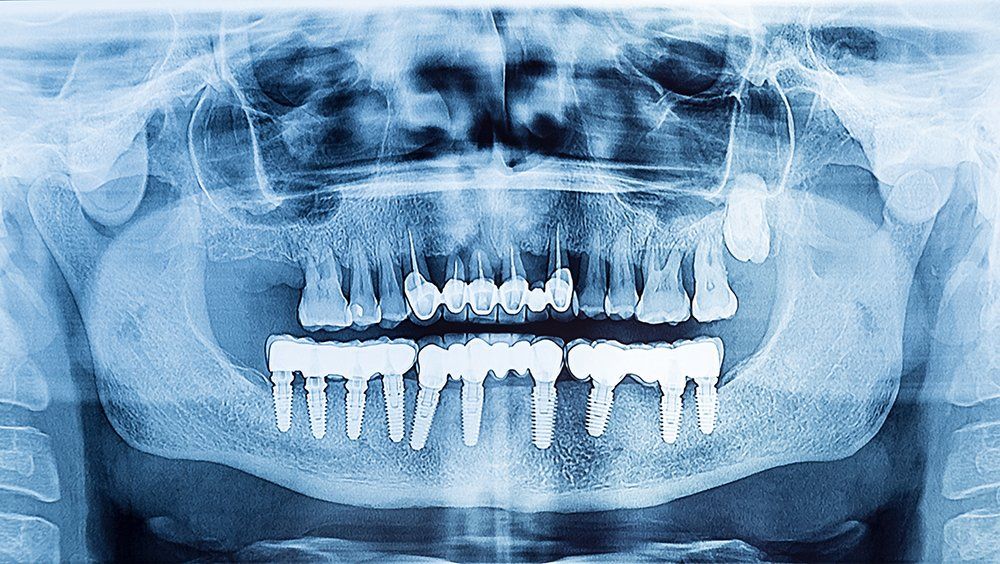

Radiologia odontoiatrica Digitale e Dentalscan

La radiologia odontoiatrica digitale e il Dentalscan consentono di ottenere immagini tridimensionali ad alta precisione per valutare denti, mascella e strutture ossee. Questa tecnologia è particolarmente utile nella pianificazione di interventi odontoiatrici complessi, garantendo una diagnosi dettagliata con minori dosi di radiazioni rispetto ai metodi tradizionali.